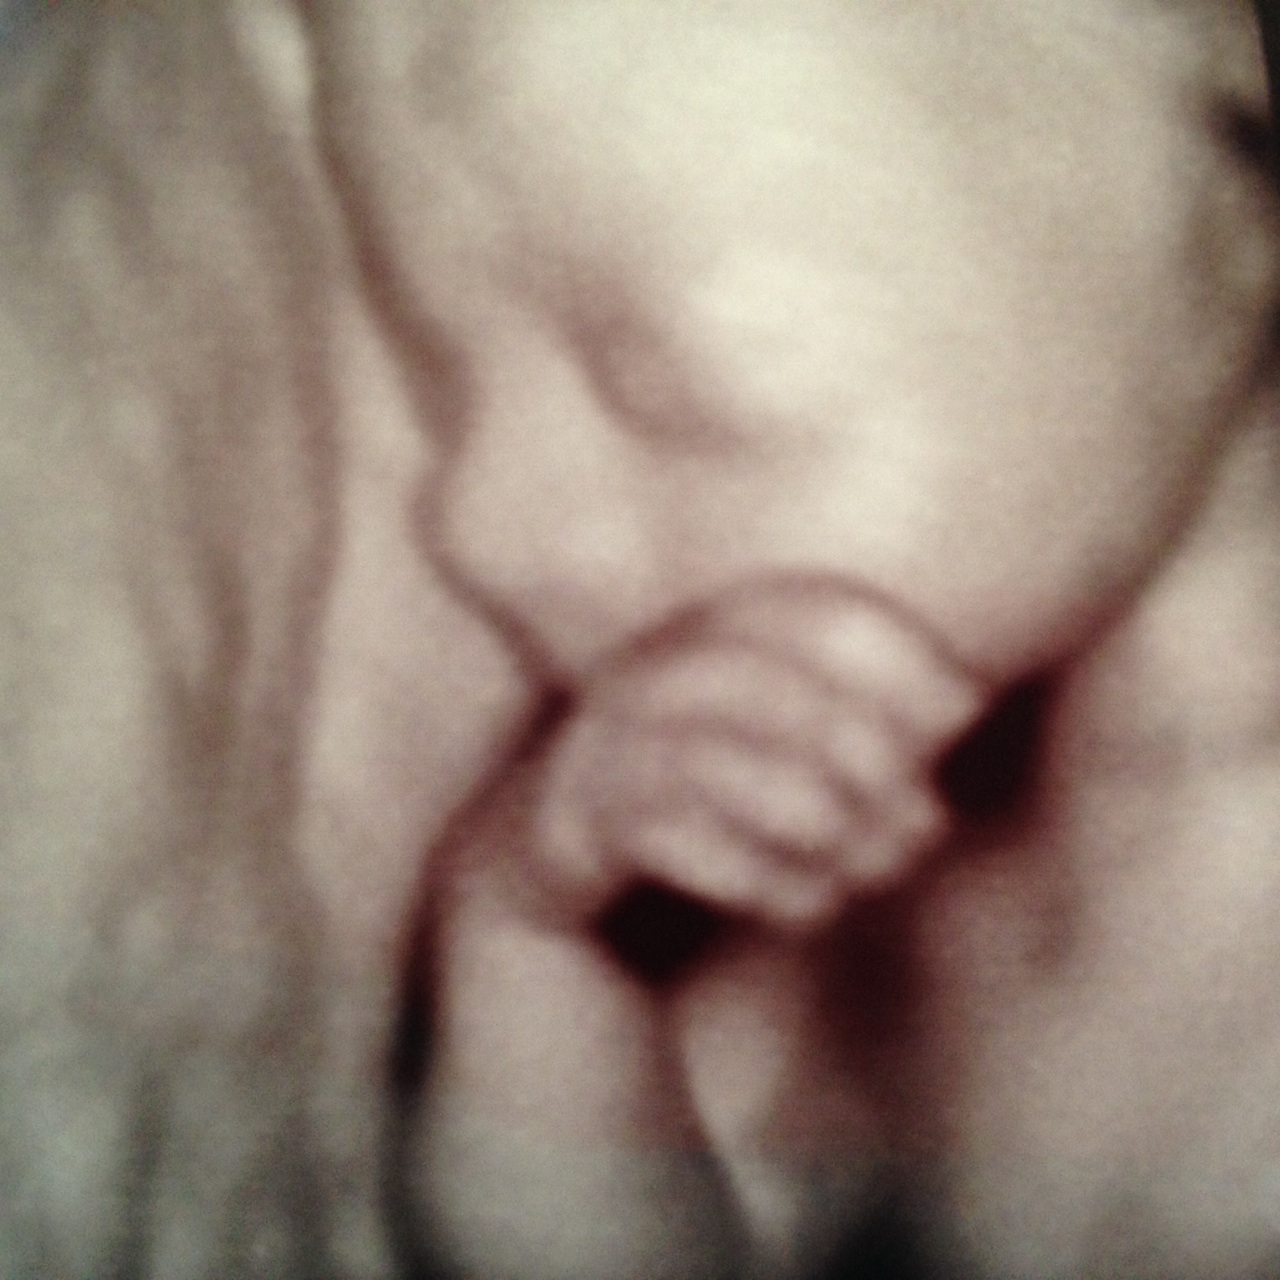

(and yes, these are actual 3D ultrasound pictures of Ella – she looks great already!)

Enjoy your alone time there in my belly – 26 weeks down, up to 14 more to go! Oh, and if you don’t mind, let’s make this birth thing a good experience for everyone involved. Thanks.